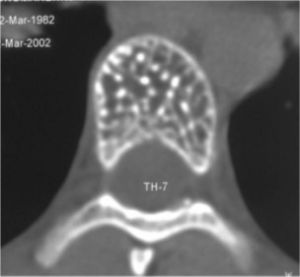

Рис.№ 2. КТ Th7 позвонка. Поражение гемангиомой всего тела Th7 позвонка. |